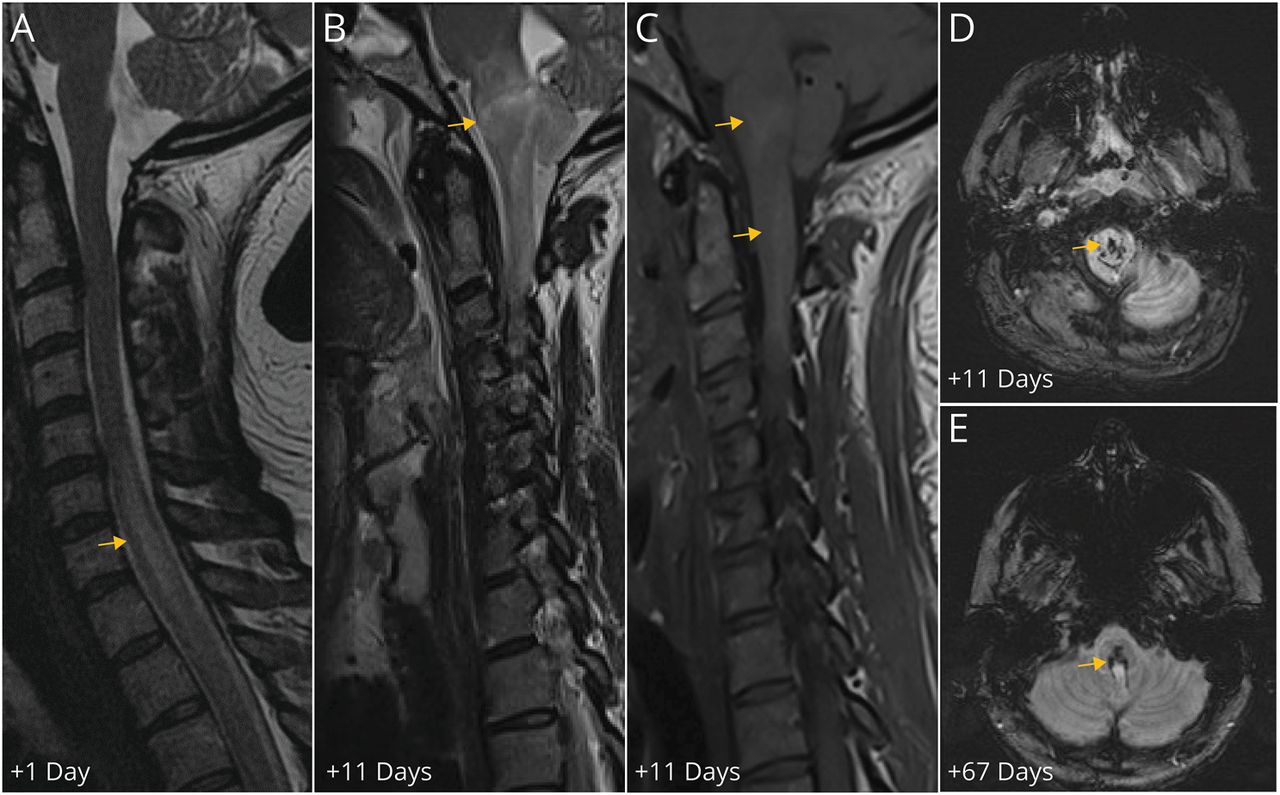

一个43岁的女人出现急性双边下肢无力,尿潴留,提升感知损失10天后发展上呼吸道感染症状。鼻咽拭子显示SARS-CoV-2 PCR检测阳性结果。神经系统检查弛缓性截瘫和T4感官层次。脊柱MRI在24小时显示对比度增强和中央t2加权hyperintensity扩张C5-T12 (图1一个)。主动脉造影是正常的。同一天,CSF证明226红细胞/μL(正常< 5 /μL)脑脊液细胞增多(949白细胞/μL,正常< 5 /μL,中性粒细胞93%),高蛋白质(210 mg / dL,正常15-45 mg / dL),和高免疫球蛋白(Ig) G指数(0.82,正常< 0.61)。CSF传染病研究,包括脑膜脑炎面板(Biofire Filmarray),单纯疱疹病毒(HSV) PCR,水痘带状疱疹病毒(带状疱疹)血清学SARS-CoV-2 PCR,和自身免疫性脊髓病神经抗体面板(梅奥诊所实验室),显示出负面结果。艾滋病毒血清学、抗核抗体(ANAs),水通道蛋白(AQP) 4免疫球蛋白和髓少突细胞糖蛋白(MOG)由细胞免疫球蛋白抗体测定(CBA)显示负面结果。血小板、凝血酶原时间(PT)和活化部分血栓形成质时间(APTT)是正常的。预防(40毫克每天)皮下注射依诺肝素是管理。

小组展示了矢状t2加权图像与分散中央线信号异常扩大优从C5-6 T11-T12(胸组件和相应的t1加权充当序列不包含在这张图片)在24小时。面板B显示了信号异常优的重大进展到脑干在矢状t2加权图像相关precontrast t1 hyperintensity从疑似高铁血红蛋白(C)和相应susceptibility-weighted成像(瑞士)hypointensity 11天(面板D)。E面板显示持久性的血副产品在瑞士(含铁血黄素,箭头所示)67天。

她收到了1 g的四甲基强的松龙(IVMP) 5天(11天后神经症状),但发展到四肢瘫痪和呼吸衰竭,所以血浆置换是发起。重复的脊椎和大脑核磁共振(11天后神经症状)显示扩展的t2加权hyperintensity优与新出血了脑干precontrast t1 hyperintensity (图1中,B和C)和susceptibility-weighted成像(瑞士)hypointensity (图1 d)。重复CSF分析(12天后神经症状)显示5红细胞/μL, 5白细胞/μL淋巴细胞(51%),31日mg / dL的蛋白质,和高免疫球蛋白g指数(1.09)。静脉注射免疫球蛋白(丙种球蛋白)管理(2毫克/公斤总剂量超过5天),另一个5天的1 g IVMP管理,其次是口服强的松锥(60毫克每日,锥形每周5毫克)。

她四肢瘫痪和机械通风。重复神经影像学在2个月显示改善低颈t2加权hyperintensity和演进瑞士hypointensity髓质(图1 e)。在3个月,扩大残疾状态量表(eds)为9.0,和修改兰金得分(夫人)5。